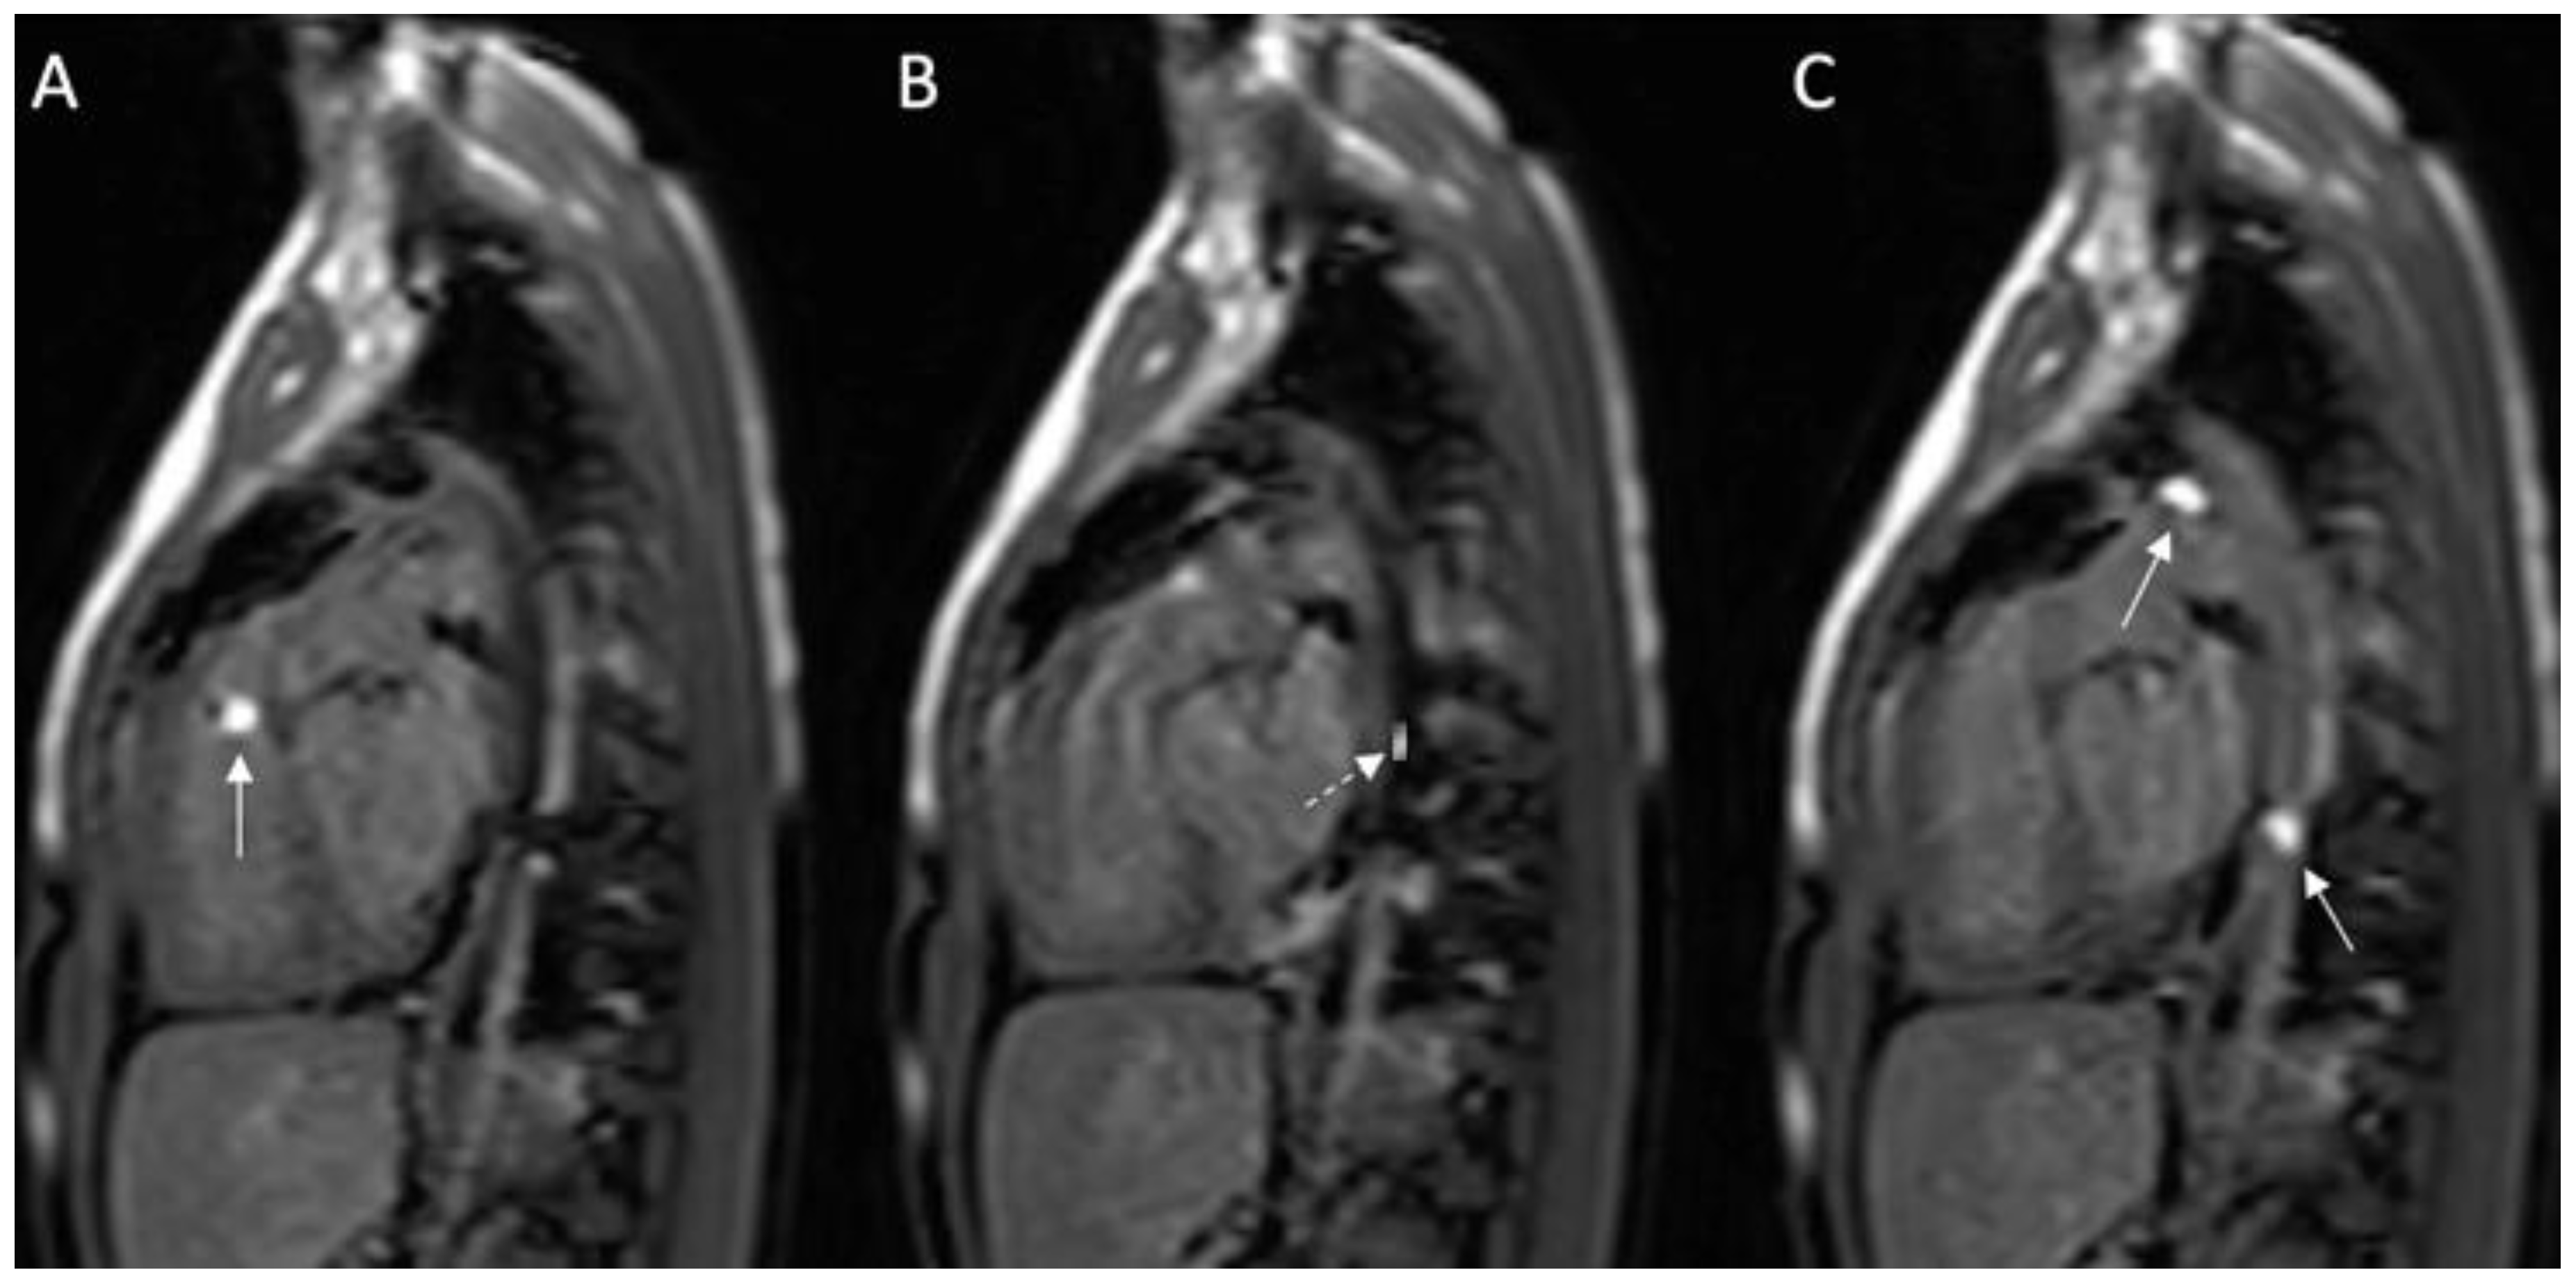

Total pulmonary blood flow assessment was done by summing the flow in the right pulmonary artery (RPA) and the left pulmonary artery (LPA) distal to PDA entrance, the approach based on the assumption that total pulmonary flow can be more accurately quantified by measuring flow in each branch artery [9]. Cardiac output was calculated by measuring blood flow in the ascending aorta as previously described [10]. The total pulmonary blood flow was calculated using the measured RPA and LPA net antegrade blood flow volume [11]. A 6 French balloon wedge catheter was used to perform the CMR-guided RHC procedure. Using the Philips interactive scanning mode guidance (Philips Healthcare), the interventionalist advanced the gadolinium-filled balloon tip of the wedge catheter and MR-conditional guidewire (Emeryglide MRWire Nano4Imaging, Aachen, Germany) (Figure 4). Magnetic resonance imaging provided excellent soft-tissue contrast for completing the right heart catheterization, including 3D reconstruction of the aortic arch, PDA, and branch pulmonary arteries (Figure 5).

Figure 4.

(A–C): Series of images during the invasive cardiac magnetic resonance (CMR) in this case. (A) Gadolinium-filled balloon in right ventricular outflow tract (arrow); (B) MR-compatible wire placed prograde across the patent ductus arteriosus (PDA) into the descending aorta; (C) Two gadolinium-filled balloons positioned within the PDA and descending aorta. Solid white arrow: gadolinium-filled balloon; dashed white arrow: MR-compatible wire.